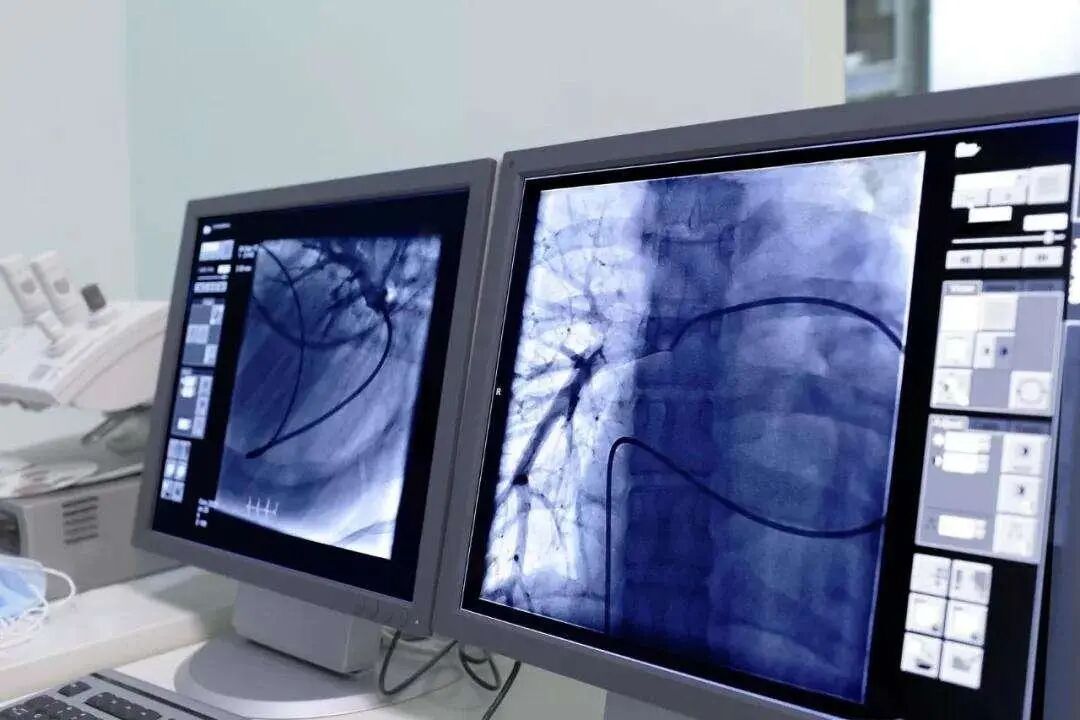

冠状动脉造影(coronary angiography)是一种有创性检查方法,通过在血管内插入导管,并注入造影剂,来观察冠状动脉是否存在狭窄、堵塞等问题。

它被视为诊断冠心病的“金标准”,能够直接显示冠脉的病变程度和位置,并且能够指导后续治疗方案的制定。

冠脉造影是一种有创性检查,需要在血管内插入导管,并注入造影剂。